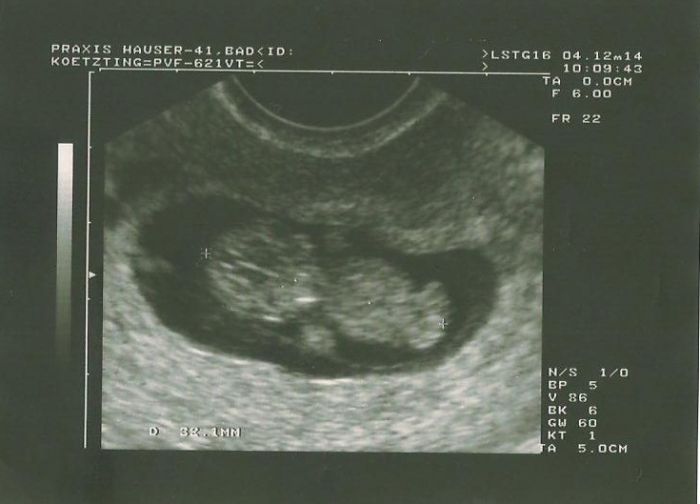

dnes 10+0 máme 3,2cm.. Vše je jak má být..

Doktor mne velice překvapil!! Cituji: Troufnu si říci, s malinkou rezervou, že tam vidím pinďoura!!!!

Mario moc gratuluju, krásná fotečka.Tak možná má doktor pravdu ;) Merunko nic neboj na Tebe určitě čeká miminko, které si Tě vybralo za maminku.Dneska jsem mněla ovulací přesně podle kalendáře (dělala jsem si test),tak to vypada, že je všechno v pořádku.Cico přítel miluje linecké,tak ho určitě vyzkouším